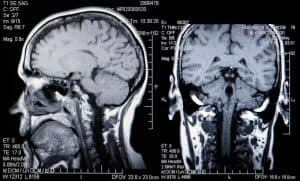

The company’s system analyzes scans for signs of weakened or distended blood vessels, a known cause of aneurysms. Once detected, the system automatically notifies neurovascular specialists to confirm and process the next steps. The system helps experts detect the signs of aneurysms earlier to prevent catastrophic outcomes.

Manual detection is slow, and humans can sometimes miss signs due to outside factors like fatigue or distraction. With machines, powerful processing capability helps ensure details don’t get missed—something that could save more people each year, considering around 3% of the population currently carry the conditions for an aneurysm.

With AI powering the bulk of data processing, the hope is to catch the signs of aneurysm earlier and with greater frequency without additional labor on physicians and specialists who are already swamped with patients. Machines are capable of examining a significant number of images in a short period of time, while humans can step in to manage diagnosis and treatment.